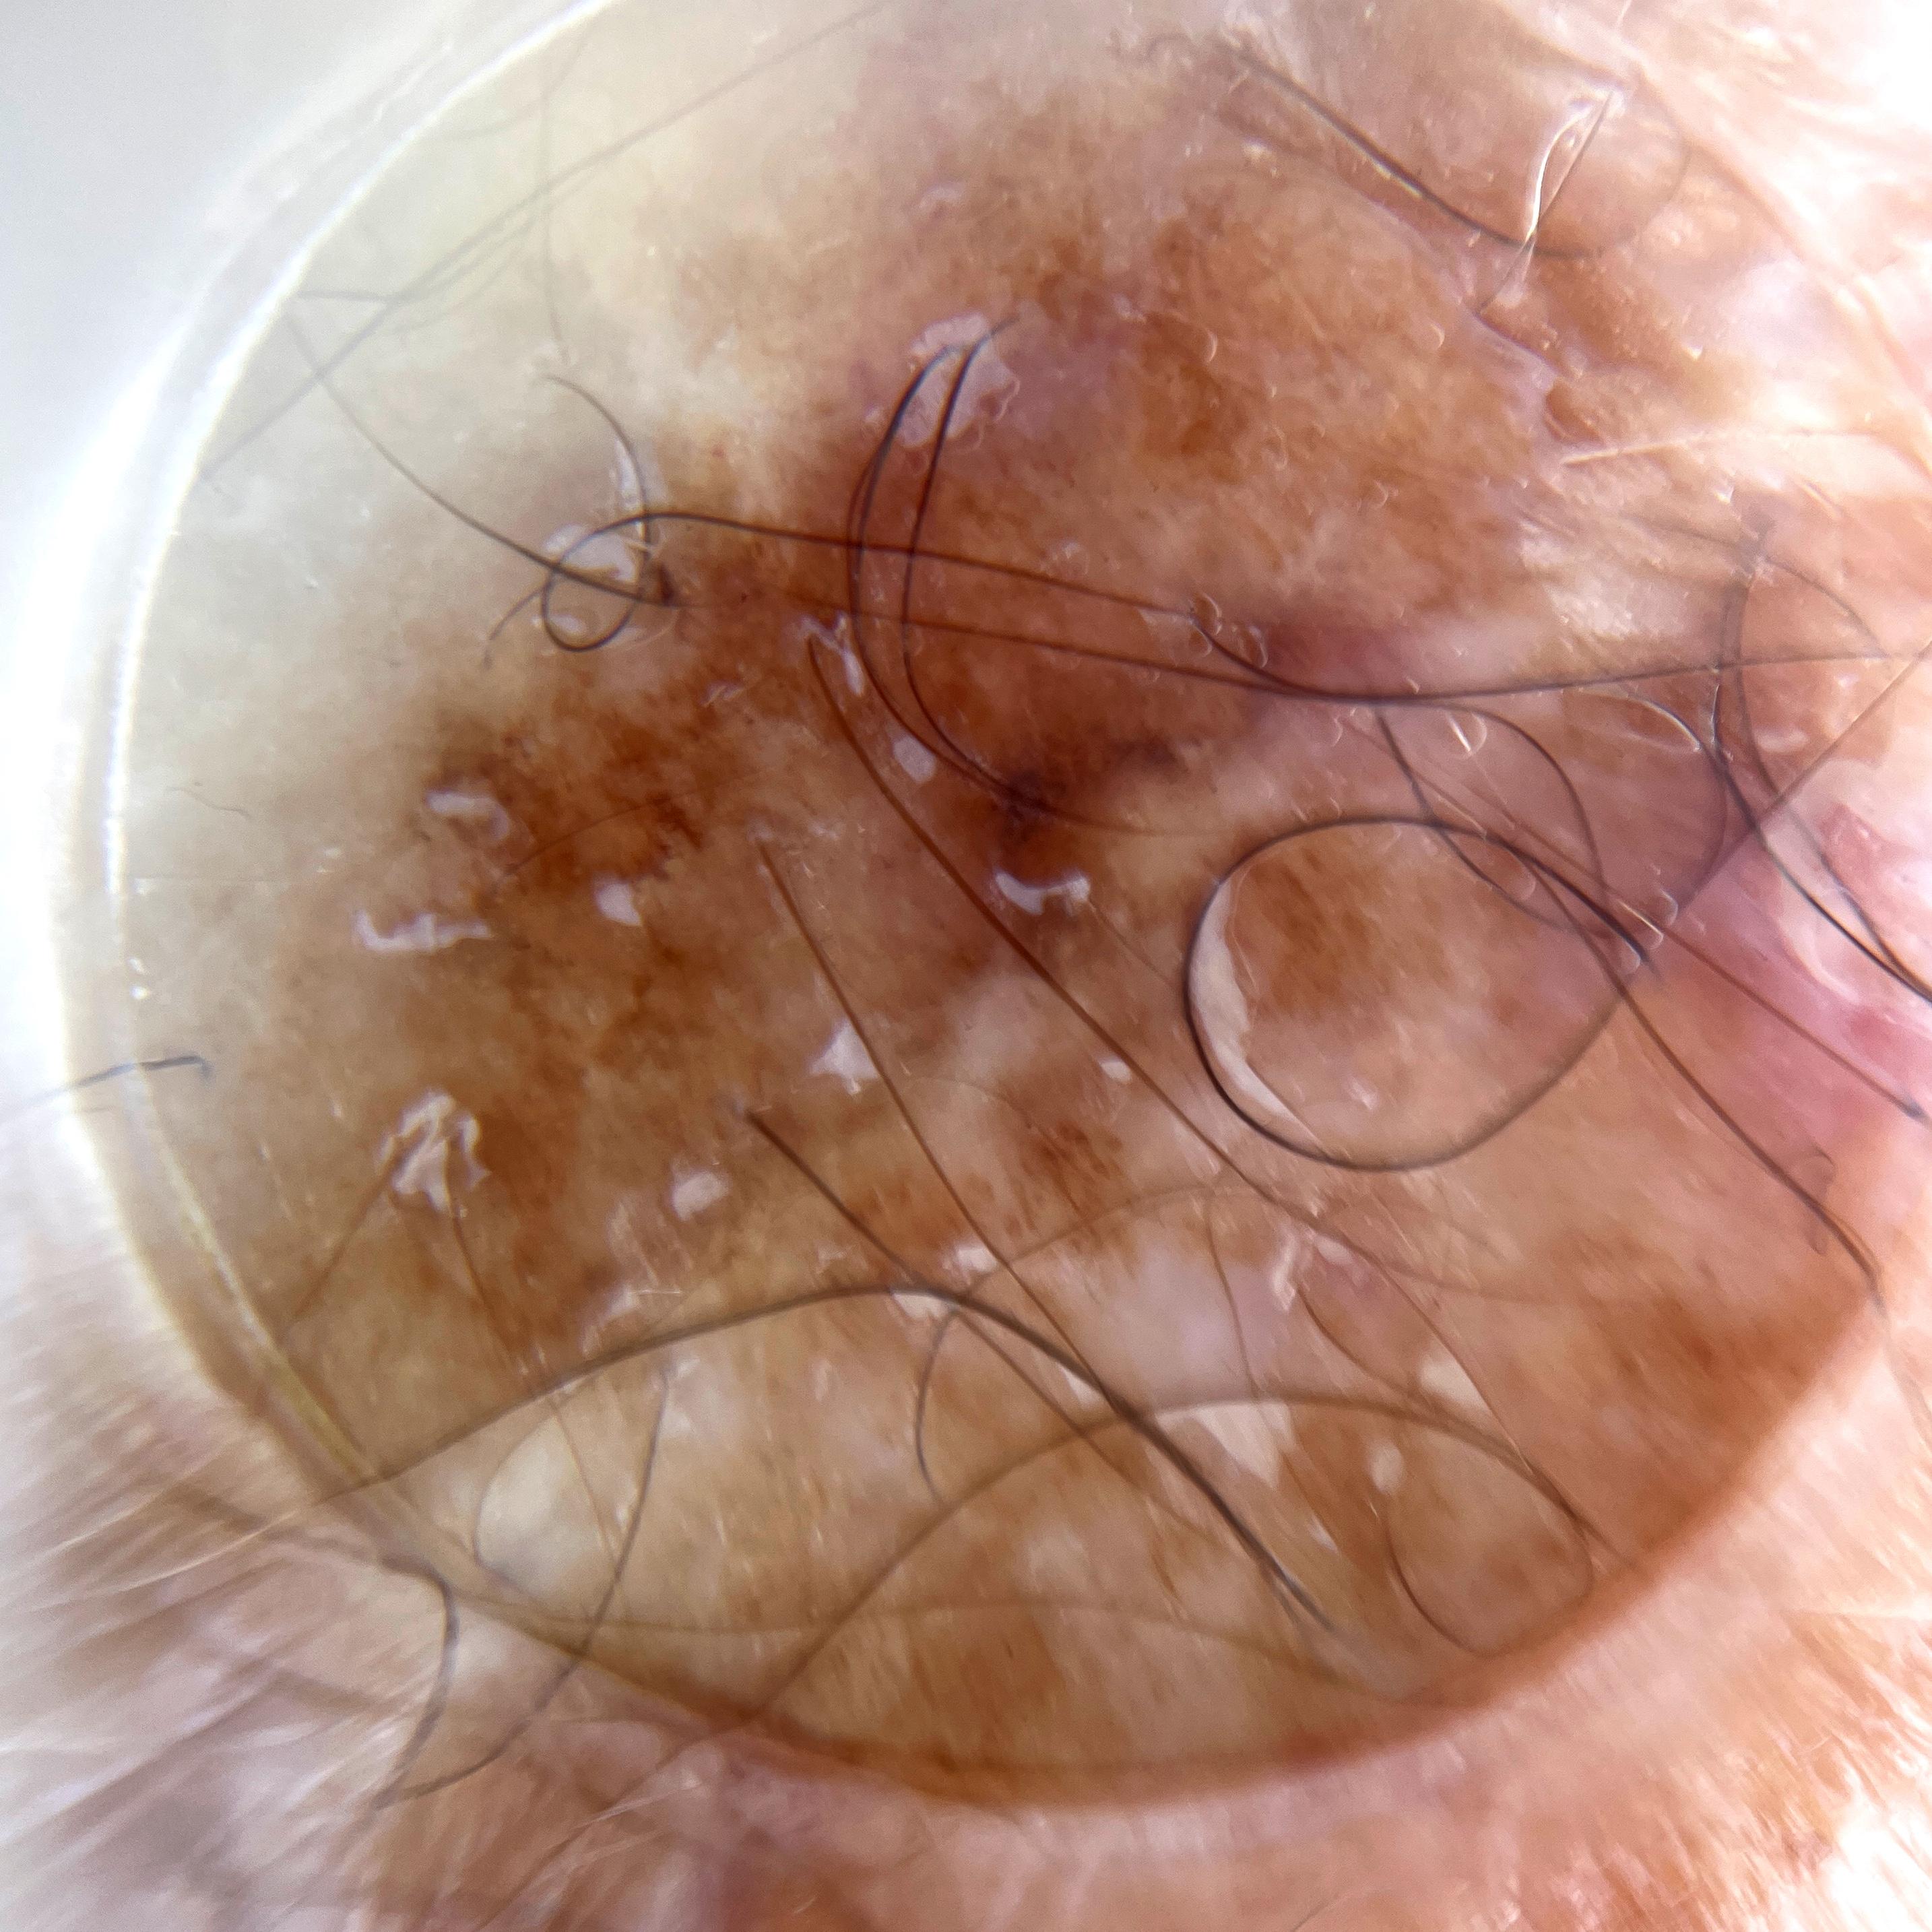

ISIC_7521238

MEL-SELF Trial, https://www.sydney.edu.au/medicine-health/our-research/research-centres/melself-project.html

acquisition_day 258

age_approx 80

anatom_site_1 Upper extremity

anatom_site_general upper extremity

diagnosis_1 Benign

diagnosis_confirm_type single image expert consensus

fitzpatrick_skin_type I

image_type dermoscopic

personal_hx_mm True

sex male